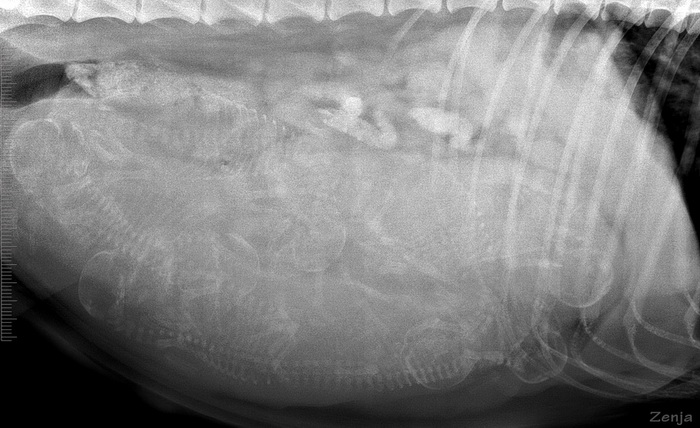

Zenja zur Lewitzperle HD-A1, CEA/PRA/Kat./Dist./MPP-frei, MDR1(+/+) DM N/N, IPD N/IPD, CEA genetisch Carrier |